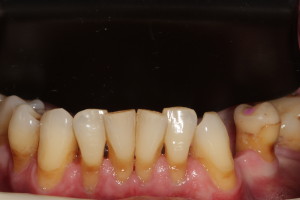

Pacjent lat 60, duże recesje dziąseł, niewyedukowany w zakresie prawidłowej higieny jamy ustnej. Został skierowany na higienizację profesjonalną przez lekarza prowadzącego. Na pierwszej wizycie siekacze dolne pacjenta wyglądały tak: zdjęcie 1, zdjęcie 4.

Widać wyraźnie, że kamień i gruba warstwa płytki bakteryjnej wywołał stan zapalny dziąseł – są przekrwione, i opuchnięte. Higienistka wykonała skaling naddziąsłowy skalerem EMS, wypiaskowała zęby piaskiem Air-Flow Plus oraz wypolerowała pasta polerską. Po zabiegu różnica wyglądzie zębów jest diametralna: zdjęcie 2, zdjęcie 5.